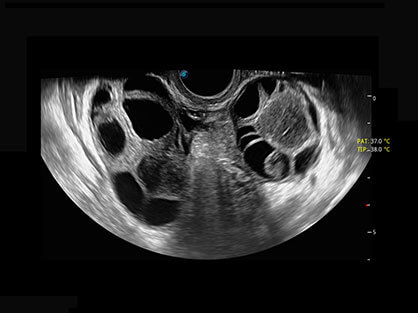

• AVC Follice卵泡自动测量

卵泡结构的自动识别和测量,可显示多组测量数据。

• 专业盆底应用

大角度腔内容积探头,可完整包络子宫及盆底结构,充分展示组织结构毗邻关系。

临床图